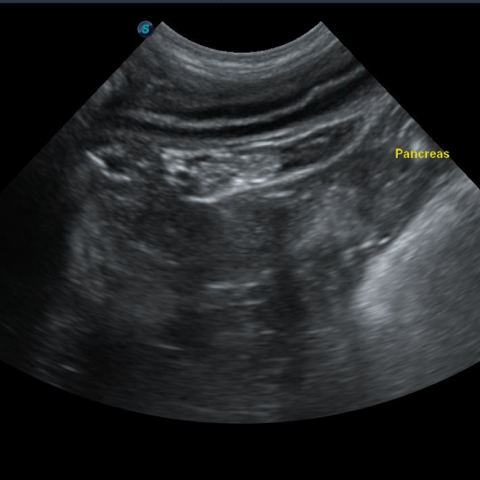

식이성, 특발성, 면역성 원인으로 생기는 췌장염은 구토, 설사, 식욕저하를 일으키고, 복통이 심한 질환 입니다. 다양한 기저질환에 의해 발생하여 만성화 되어 재발하는 경우가 많아서 만성적인 췌장염 관리와 합병증 관리가 필요합니다.

각 상황에 맞춰 분변검사, 혈액검사, 방사선검사, 초음파 검사를 진행합니다.

췌장염